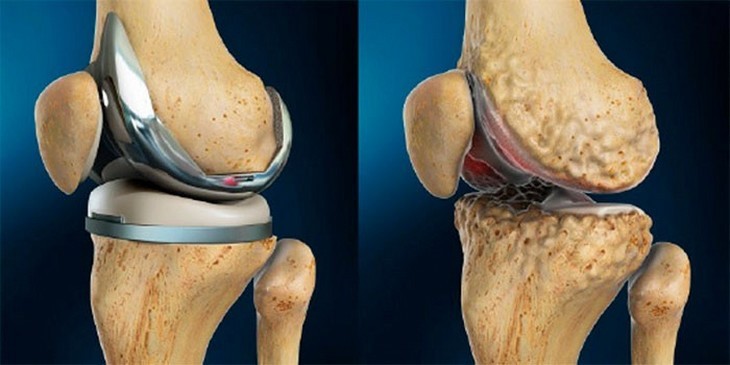

Ендопротезування колінного суглоба

Ендопротезування суглоба – це операція по заміні компонентів суглоба імплантантами, які мають анатомічну форму здорового суглоба і дозволяють виконувати весь обсяг рухів. Після подібних операцій пацієнт забуває про болі в суглобах і повертається до активного життя.